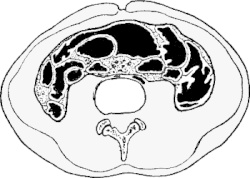

FIG. 9.—Antero-posterior section; shape of cavities with and without corsets. |

Effects of the Pressure on the Abdomen,—The abdominal

cavity has far greater pressure and much more marked

alteration in shape to stiffer than the thoracic. The change

in its lateral walls has been considered in part, and figured

in Figs, 3 and 4. In antero-posterior section (Fig. 9) the

deformity to which I would especially direct attention is

the close approximation of the belly-wall to the spinal

column, and the bulging of the hypogastrium. I have

pictured no exaggerated instance, but give the tracing from a

muscular young woman who has never been pregnant, with

an abdominal wall of better vigor than common.